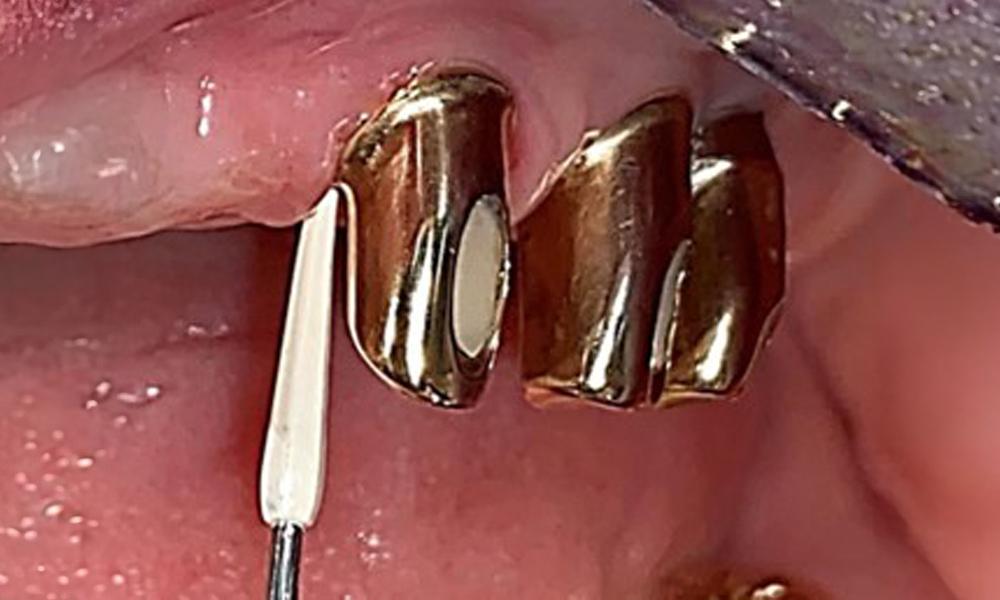

Occlusal view: Maxilla with tooth and implant-supported telescopic prostheses.

Fig. 2: Occlusal view: Maxilla with tooth and implant-supported telescopic prostheses

The dental findings are as follows: Combined removable implant and tooth-supported telescopic prostheses on implants 15, 13, 21, 23, 24, 25 and tooth 11 (Fig. 1, Fig. 2, Fig. 3). The patient was fitted with a fixed mandibular denture. Adequate bridges were present over 37 to 34 and 45 to 47 (Fig. 4), the crown margins were intact and there were no active caries. A composite filling with a marginal gap was present on tooth 43. There was mandibular gingival recession, exposing 1 to 3 mm of root surface. This also applies to 11.